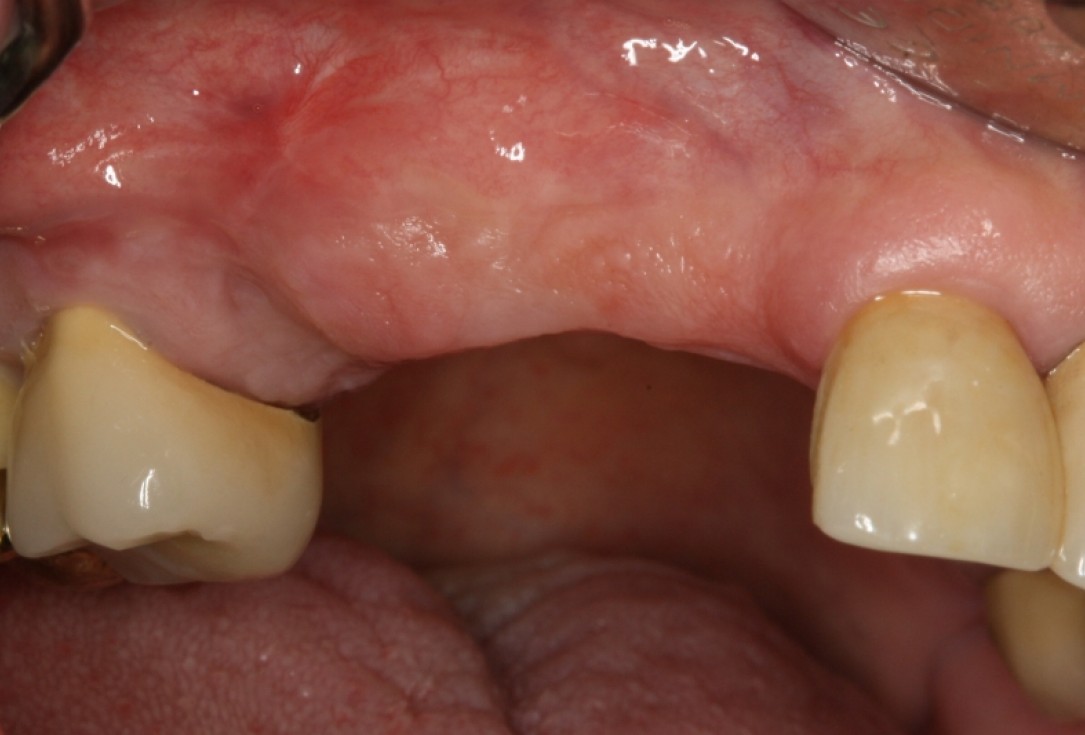

Initial situation - A young female 34 years old lost her front teeth in an surfing accident and she had a 5 unit bridge supported by her upper left lateral and right canine. The restoration failed and both supporting crowns have exposed and leaking margins.